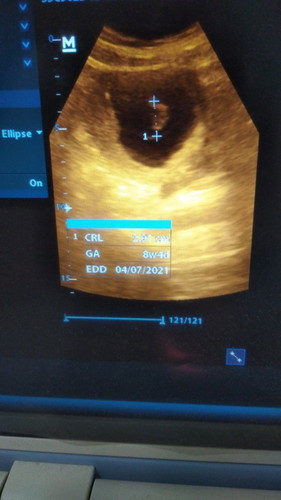

Adakah yang mengalami seperti saya? Kemarin pas umur kehamilan 8 week baru kelihatan kantong saja. Terus kemarin pas umur 12 weeks sy USG lagi dan Alhamdulillah sudah ada janinnya, tapi ukuran janinnya kecil banget tidak sesuai dengan umur kehamilan. Dan pas di USG terlihat usia janinnya masih 8 weeks. Padahal kalau dihitung dari hari terakhir mens usianya sudah 12 minggu. Kata bidannya nanti 2 Minggu lagi suruh kontrol lagi. Minta doanya ya bunda2 semoga nanti janinnya ada perkembangan yang positif. Apakah ada yg pernah mengalami hal ini?#bantusharing